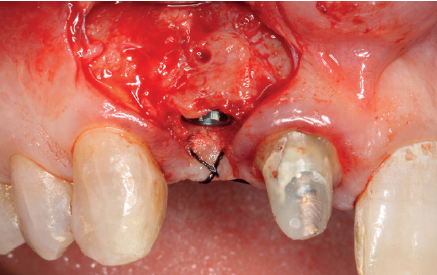

(Figuras 5 y 6). Con esta imagen se procede a la apertura de un colgajo y la explantación del implante. Se retira también la corona situada en el diente 1.1 para poder realizar otra corona que servirá para apoyar el provisional en extensión para la zona del 1.2, mientras cicatriza la primera intervención. En este primer abordaje se coloca también un injerto en bloque obtenido de la rama mandibular que se fija con un microtornillo en la zona a regenerar donde se ha perdido la cortical vestibular. Una vez fijado y posicionado, se rellena alrededor del injerto en bloque con hueso particulado obtenido con un bone-scraper de la misma zona donante embebido en PRGF-Endoret para una mejor fijación y viabilidad celular (Figuras 7-9).